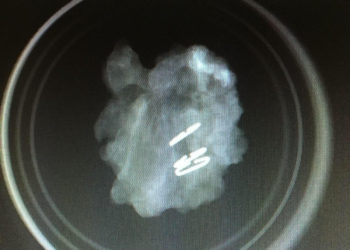

La nueva técnica oncoplástica recién implantada en el HUCE por la Unidad de Mama viene a suplantar las tumorectomías o ...

La nueva técnica oncoplástica recién implantada en el Hospital Universitario de Ceuta (HUCE) por la Unidad de Mama viene a suplantar ...